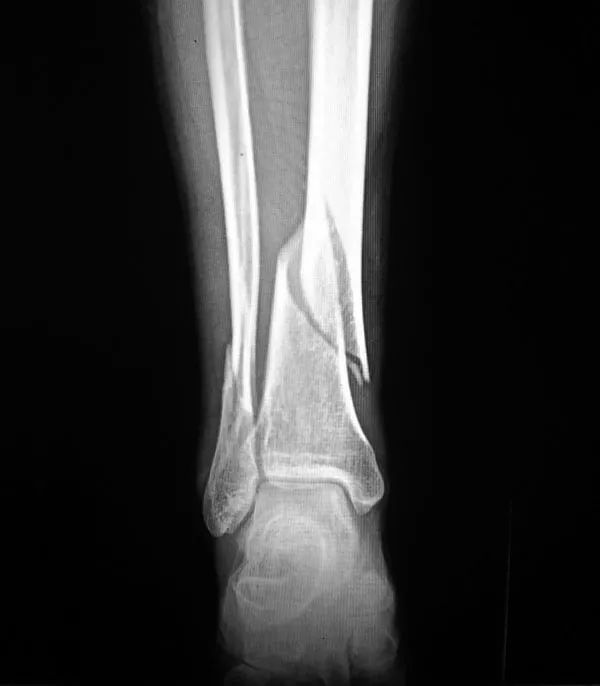

2、骨折:骨質(zhì)疏松癥最常見的并發(fā)癥是骨折,輕微外力即可導(dǎo)致骨折,60歲以上老年人骨質(zhì)疏松并發(fā)骨折者高達(dá)12%。多見咳嗽打噴嚏時(shí)、彎腰屈伸撿東西、回頭轉(zhuǎn)身及摔倒等易發(fā)生骨折。骨量丟失20%以上時(shí)易發(fā)生骨折,輕者可使活動(dòng)受限,重者須長(zhǎng)期臥床,給社會(huì)和家人造成很大負(fù)擔(dān)。老年人骨折可引發(fā)或加重心腦血管并發(fā)癥,導(dǎo)致肺感染和褥瘡等多種并發(fā)癥的發(fā)生,嚴(yán)重危害老年人的身體健康,甚至危及生命,死亡率可達(dá)10%~20%。